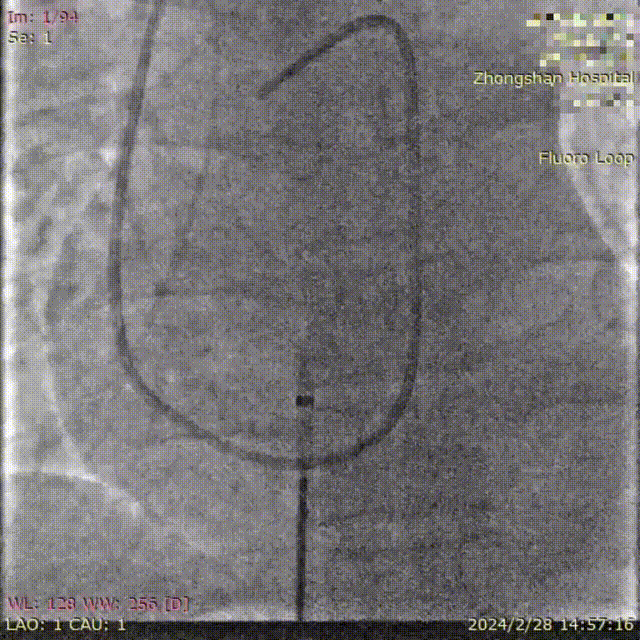

葛均波院士为患者植入FreeFlow经皮房间隔分流器,在DSA的监测下分流器左盘通过输送鞘管到达左心房并释放;回撤输送鞘管,释放分流器右盘;行牵拉试验,观察分流器形态、位置、左右心房分流情况;旋转输送钢缆将分流器完全释放;撤离输送钢缆、输送鞘管,手术圆满完成,分流器释放性能、输送系统操作性能均表现良好。复查心超/DSA,分流器位置、大小、形态合适,对周围结构无影响,清晰可见右向左分流。

牵拉试验